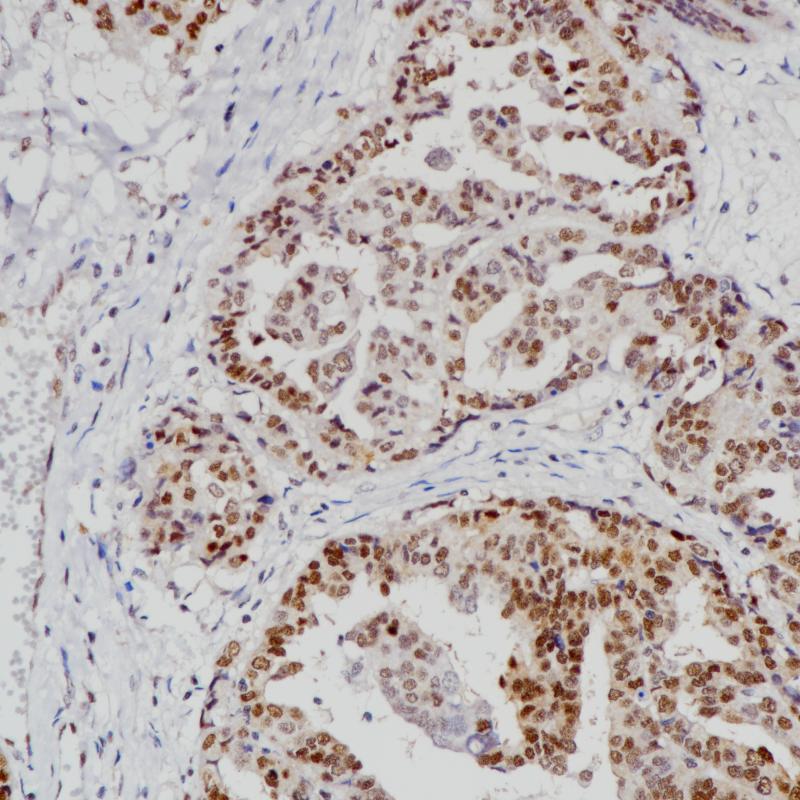

子宫内膜癌MGMT(BP6217)染色

MGMT,O6 -甲基鸟嘌呤-DNA甲基转移酶,是一个DNA修复酶,参与对DNA中O6 -甲基鸟嘌呤(O6-MeG)生物效应的细胞防御。MGMT启动子甲基化将导致 MGMT基因的沉默,从而减少 MGMT mRNA和蛋白的表达,因此,患者的 MGMT基因启动子区甲基化程度越高,使用烷基化药物的效果可能越好。

阳性对照

子宫内膜瘤

亚细胞定位

细胞核